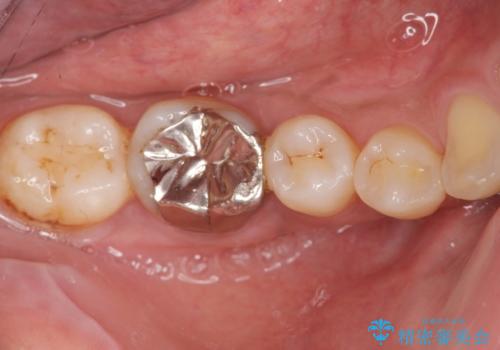

- 笑ったときに目立つ奥歯の銀歯を白くしたいという希望で来院されました。

銀歯を除去し、ジルコニアクラウンによる審美性の回復を計画します。